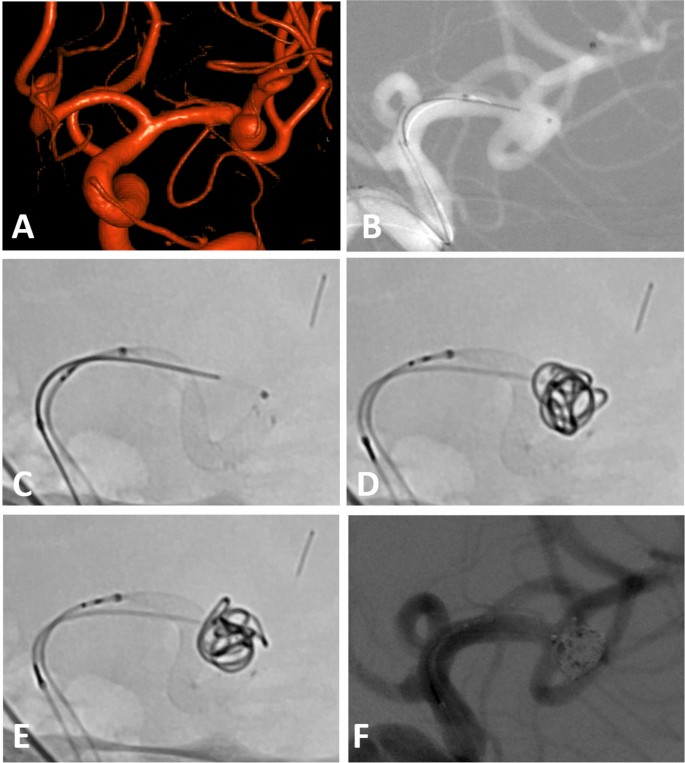

All procedures were performed using a 6F guiding catheter or an 8F long sheath with or without an intermediate catheter. In the majority of cases a jailing-technique for aneurysm access and coiling was used. Due to the small cell size re-crossing into the aneurysm after stent placement is possible but more difficult than jailing. This necessitates usually the use of two microcatheters during the intervention. After catheterization of the parent vessel and after placing the second microcatheter in the aneurysm, the stent was usually deployed only partially to allow for later repositioning. The better visibility of the stent allows for adapting the stent to challenging anatomies especially at bifurcations. To narrow the neck of a broad-based aneurysm the stent can be deployed using a push-and pull-technique to form a sort of shoulder at the aneurysm neck. This technique may eliminate the need for Y-stenting in some cases and has been described as shelf technique elsewhere11,12. An example of this technique is provided in Fig. 1.

(A) Incidental broad-based aneurysm of the left MCA in a female patient in her fifties. (B) Jailing technique with one microcatheter within the aneurysm sac and on in the inferior trunk of the MCA .(C) First position of the LVIS EVO stent with an incomplete adherence to the vessel wall and a slight kinking—note the very good visibility of the stent wires (D) Final position of the stent after partial re-sheathing and re-positioning with formation of a shoulder at the neck. The first coil is already within the aneurysm sac. (E) Final position of the framing coil using the repositioned stent as a scaffold (F) Final angio run after placement of the last coil.